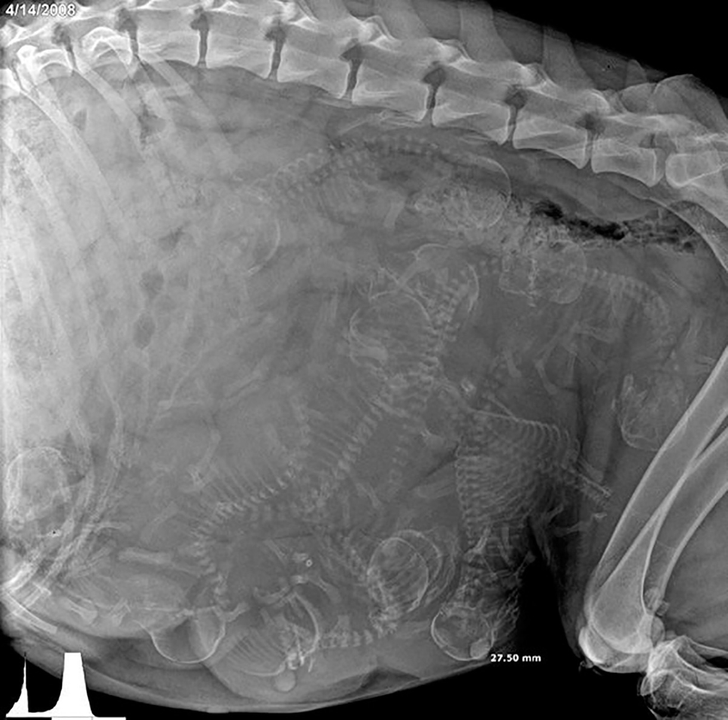

1. Рентген беременной собаки.

© GoodGriefWhatsNext / reddit